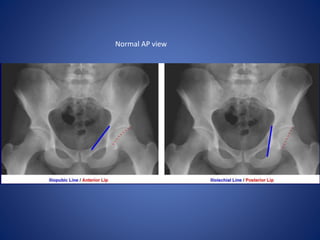

Name the views and the indication for taking

this view…..

Judet Views

Patient supine, oblique patient 45o both ways (RPO & LPO).

Taken to evaluate fractures of acetabulum.

Normal AP view

LPO

AP

RPO

Judet Views Patient supine,oblique patient 45o both ways (RPO & LPO). Taken to evaluate fractures of acetabulum.